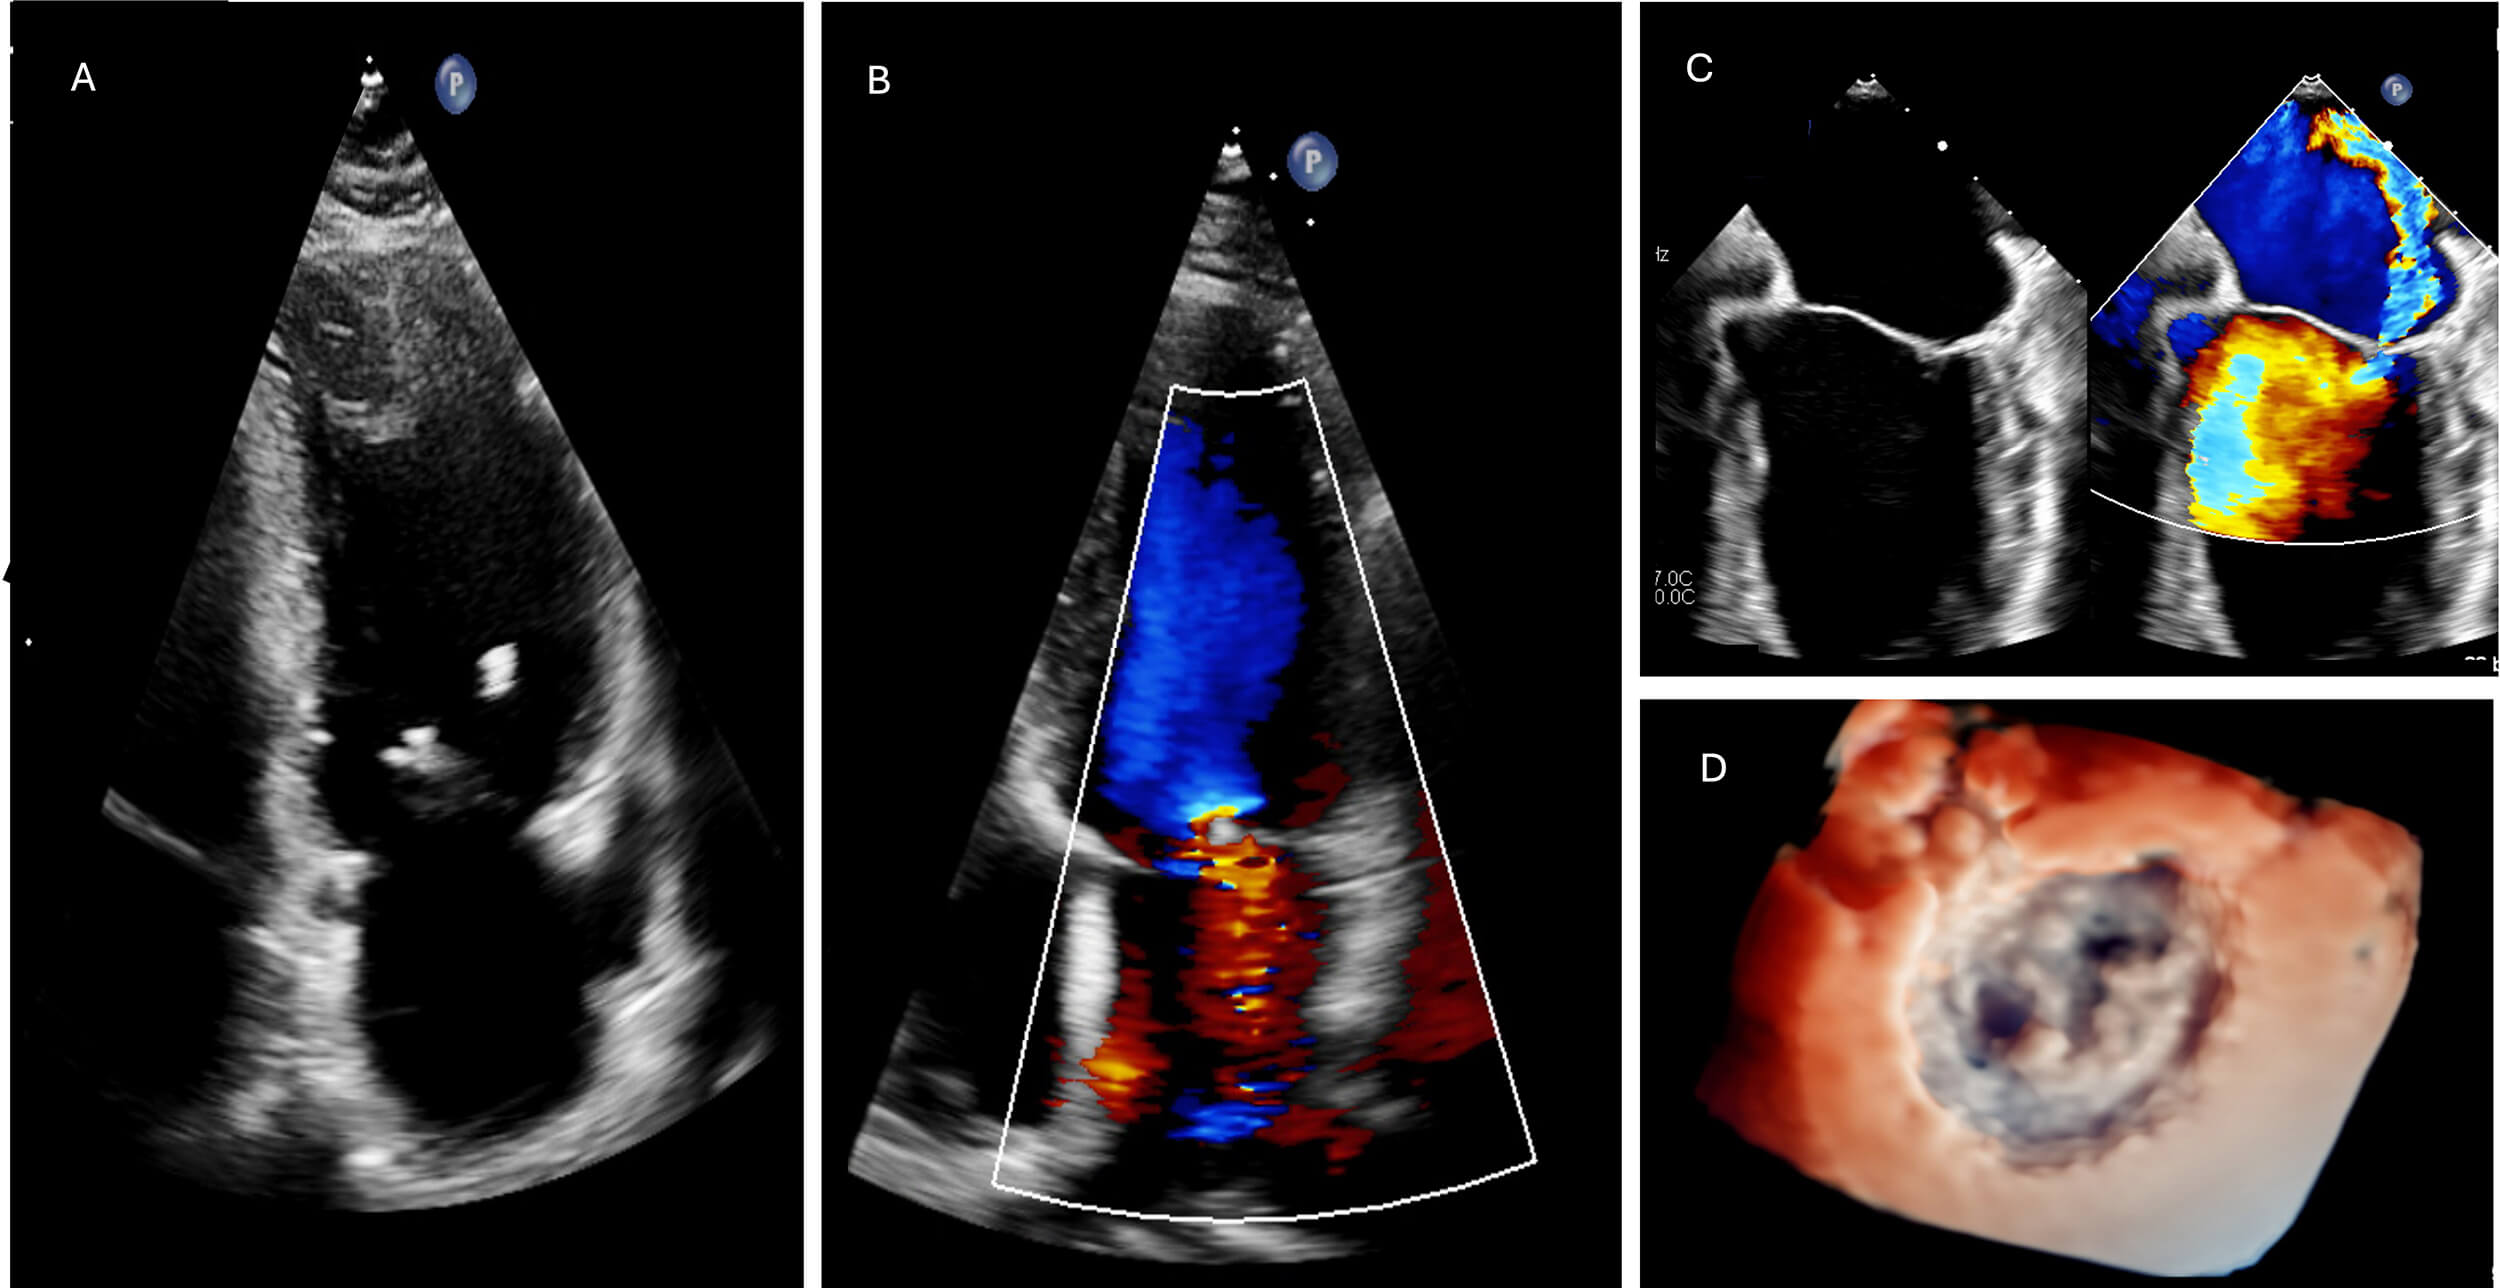

Echocardiography showed severe mitral regurgitation with an anterior leaflet vegetation (Fig. 2). Initial blood cultures were negative for growth, which was likely due to earlier antibiotic administration.

Fig. 2.

Initial transthoracic echocardiography (TTE) with mitral valve regurgitation and echogenic mitral valve lesion. (A) TTE apical 4 chamber view of the left ventricle (LV) revealing an echogenic mobile structure connected to the mitral valve, indicative of vegetation. (B) TTE apical 4 chamber colour doppler demonstrating associated mitral regurgitation (MR), further highlighting the valvular pathology. (C) Transoesophageal echocardiography (TOE) image of a zoomed 4-chamber view, providing a detailed visualization of a flail mitral valve with associated mitral regurgitation, emphasizing the severity of valvular dysfunction. (D) TOE 3D reconstruction displaying a comprehensive view of the vegetation, clearly visualizing its attachment to the ventricular side of the mitral valve.